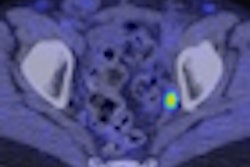

During PET imaging, radiolabeled probes are used to target and measure biological and pharmacological processes. Elixys uses a multireactor design and features disposable cassettes to simplify operations, high-temperature and high-pressure capabilities, on-demand reagent delivery, and radiation sensors and reactor vial cameras to monitor synthesis processes, according to the firm. The system also has software that can be used on smartphones and mobile tablets.